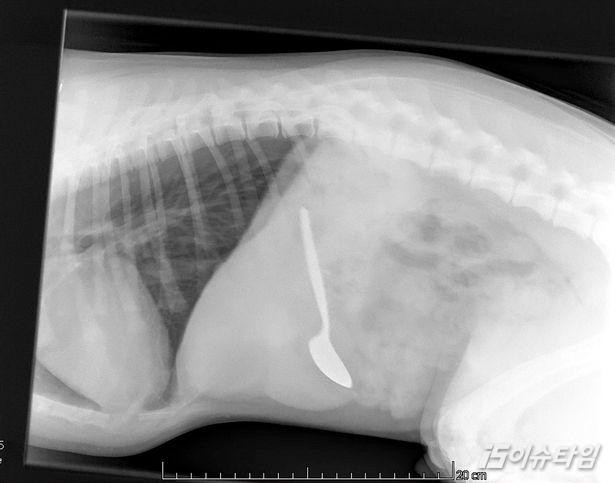

14㎝가 넘는 수저를 삼킨 강아지가 기적적으로 건강을 회복했다.[사진=SWNS.com/Mirror]

그는 곧바로 래브라도를 데리고 동물병원으로 향했다. 수의사는 "14㎝가 넘는 숟가락을 어떻게 삼켰는 지 믿을 수 없다"고 말했다.

의료진은 래브라도가 삼킨 숟가락을 찾으려고 엑스레이부터 위내시경까지 동원했다. 뱃속에 걸려있던 숟가락을 발견하곤 곧바로 수술로 빼냈다.